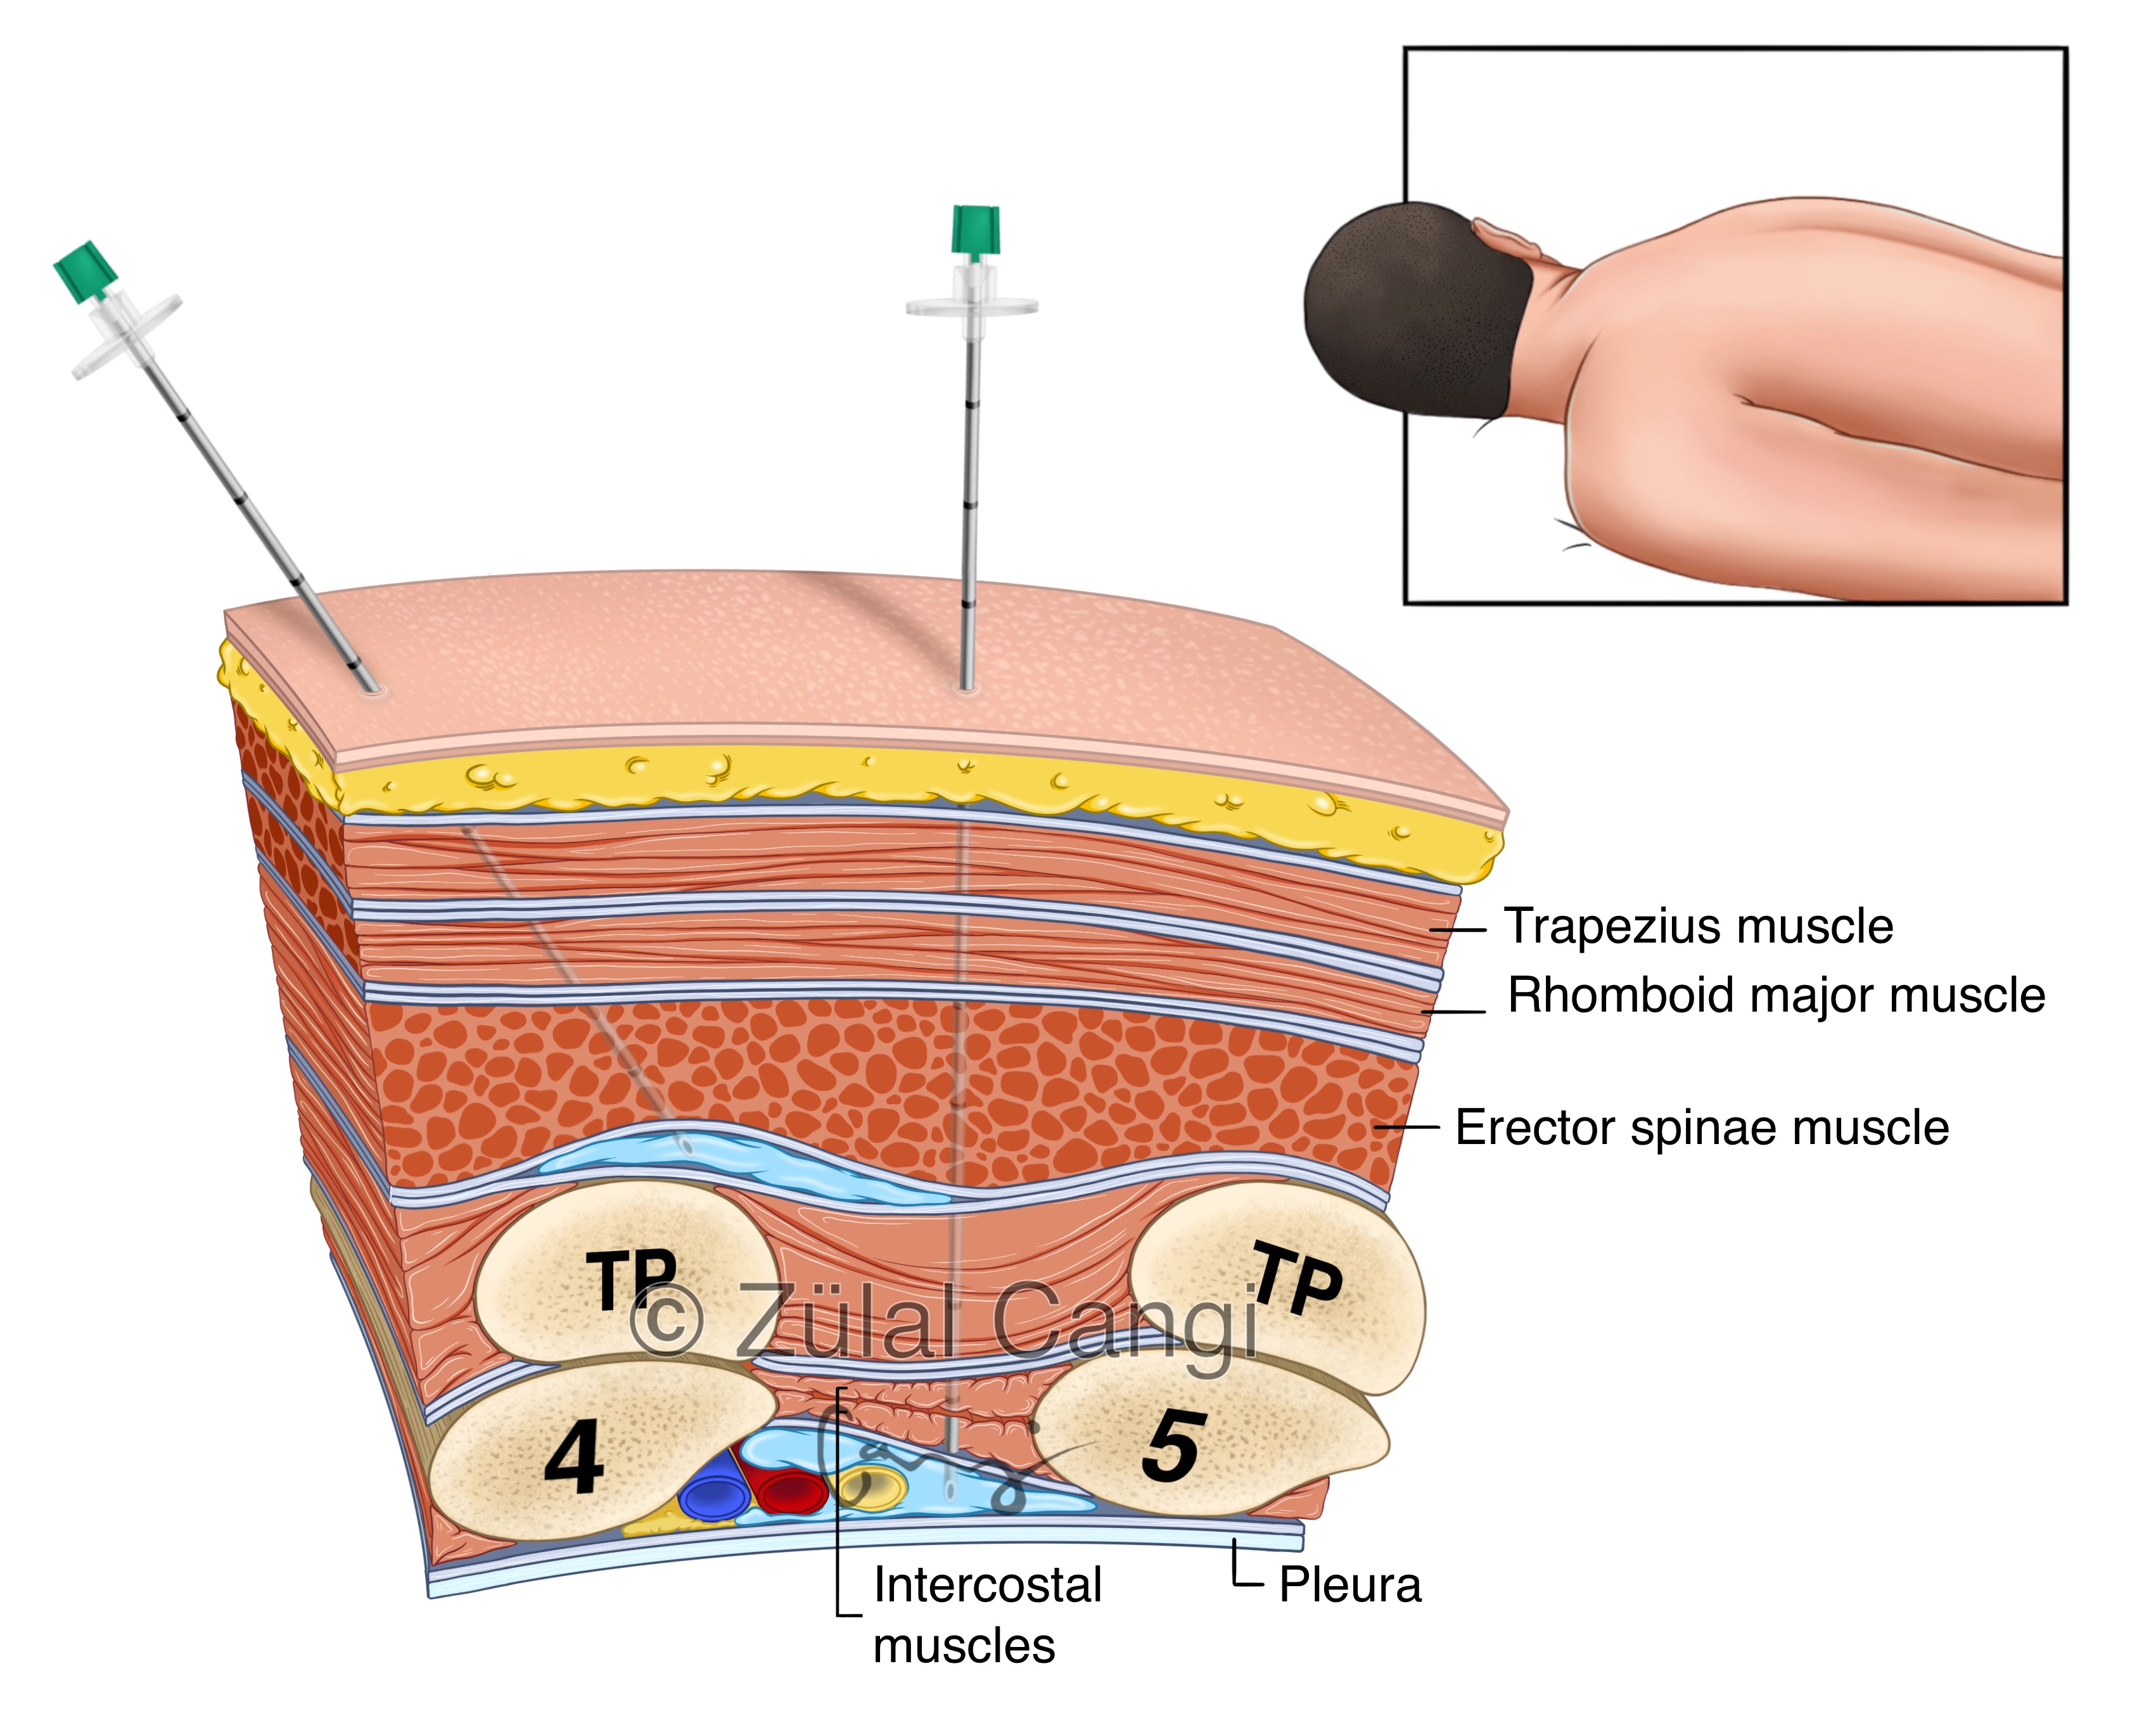

Sanatın estetiğini bilimin kesinliğiyle bir araya getiren Zülal Cangi, medikal ve bilimsel illüstrasyon alanındaki çalışmalarıyla akademik yayınlar, eğitim materyalleri ve çeşitli bilimsel platformlar için görsel içerikler üretmektedir. Amacı, bilimsel bilgiyi yalnızca doğru biçimde aktarmakla kalmayıp, aynı zamanda öğretici ve estetik bir dille görünür kılmaktır.

PORTFÖY